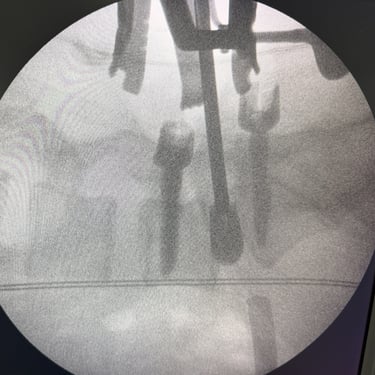

Listesis Lumbar L5–S1 por Fractura Ístmica: Estabilización con FTP y TLIF

La listesis lumbar L5–S1 por fractura ístmica se produce por un defecto en la pars interarticularis que genera inestabilidad vertebral, dolor lumbar crónico y compromiso radicular. Cuando el tratamiento conservador no es efectivo, la artrodesis lumbar con fijación transpedicular (FTP) asociada a la fusión intersomática transforaminal (TLIF) es una alternativa quirúrgica eficaz. Este procedimiento permite descomprimir las raíces nerviosas, restaurar la alineación vertebral y lograr una fijación sólida del segmento afectado. La combinación de estabilización y fusión reduce el dolor, mejora la función y favorece una recuperación segura y progresiva.